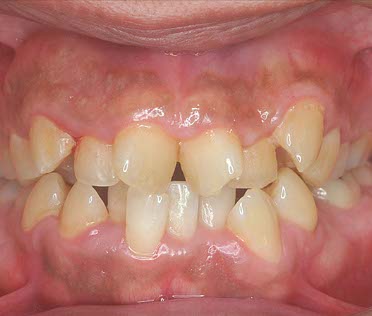

初診相談後、治療をご希望される場合は、初診検査を実施します。この検査で、患者様の現在の口腔内の状態を確認します。

顔貌・口腔内写真の撮影

レントゲン撮影

歯型の模型採取